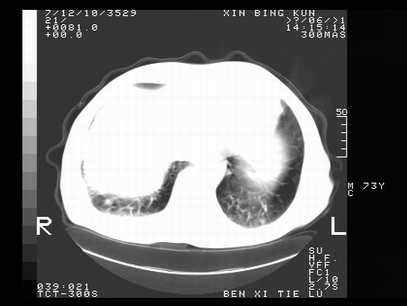

标题: CT10820:男,73岁,病史肺TB,现病史肺炎,直肠CA术后 [打印本页]

标题: CT10820:男,73岁,病史肺TB,现病史肺炎,直肠CA术后

双肺间质改变,依据病史双肺多发结节灶考虑转移,少量胸水.

1.两肺结核.2.两肺多发转移瘤.3右侧少量胸腔积液4.主动脉钙化.

双肺多发结节及条片状致密影,右侧少量胸腔积液。临床:直肠ca术后,肺tb病史。综合考虑:1 双肺转移!2 继发性肺结核合并感染!

此人病史较复杂,原有肺结核,直肠癌术后。肺部病灶形态亦呈多形性。因此,不可仅以一种病来解释肺部的病变。双肺多发的类圆形结节灶,结合病史还是首先考虑转移瘤,而双肺其余病灶还需结合化验室检查,结核或肺部感染在无其它检查资料的情况下不好排除。还是那句话----放射科医生不是开照像馆的,我们也是医生,看片一定要多结合临床及其它检查资料。要当一名合格的放射科医生,并不比当一名临床医生容易,我们可别把自已不当医生看。

两肺多发结节影,并见滋养动脉与其相连,考虑 两肺转移. 右侧胸腔积液考虑胸膜转移.

左肺上叶下叶背段,右肺中下叶见多发斑片状、条索状高密度影,兵变周围小结节影形成“树芽”样改变。 左肺上叶舌段近前胸壁处及右肺中叶内侧段见结节影。右侧胸膜腔内见液体密度区。纵隔内未见明确增大淋巴结。考虑左肺上叶舌段近前胸壁处及右肺中叶转移瘤可能性大。两肺继发型肺结核。右侧胸腔积液。

还有心包少量积液。